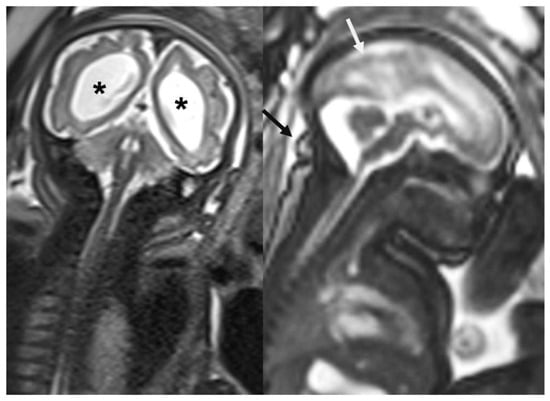

- Ribeiro, B.N.d.F.; Muniz, B.C.; Gasparetto, E.L.; Ventura, N.; Marchiori, E. Congenital Zika syndrome and neuroimaging findings: What do we know so far? Radiol. Bras. 2017, 50, 314–322. [Google Scholar] [CrossRef] [PubMed] [PubMed Central]

- Araujo Júnior, E.; Carvalho, F.H.; Tonni, G.; Werner, H. Prenatal imaging findings in fetal Zika virus infection. Curr. Opin. Obstet. Gynecol. 2017, 29, 95–105. [Google Scholar] [CrossRef] [PubMed]

| Findings | Computed Tomography | Magnetic Resonance Imaging |

|---|---|---|

| Microcephaly | Reduced skull diameter and brain volume | Reduced skull diameter and brain volume |

| Cerebellar hypoplasia | It can be observed | It can be observed |

| Cortical abnormalities | Can identify volumetric reduction in the brain parenchyma | Best examination to identify cortical abnormalities, usually diffuse and predominantly in the frontal lobes |

| Prominence of the occipital bone | Detected | Detected |

| Intracranial calcifications | Sensitive to calcifications, especially in the subcortical junction, basal ganglia, thalamus, and brainstem | Detects calcifications but with less sensitivity compared to computed tomography |

| Ventriculomegaly and colpocephaly | Frequent | Can be identified |

| Enlargement of the extra-axial cerebrospinal fluid space | Possible to identify | Best test to identify enlargement, due to impaired reabsorption of cerebrospinal fluid caused by decreased brain volume |

| Changes to the skullcap | Everted sutures and prominent occipital bones | More detailed for changes such as the “collapsed” appearance of the skull |